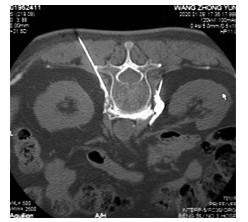

A study on the relationship between clinical and CT features and length of stay of general type novel coronavirus pneumonia patients in mobile cabin hospital

MA Gang, FENG Ke, MA Han-ning, MA Xiao-bin, YANG Xiao, MEI Bin

2021, 19(2): 316-319. doi: 10.16766/j.cnki.issn.1674-4152.001798

622 3

Abstract:

Objective  To retrospectively analyze the clinical and CT features of novel coronavirus pneumonia patients with general type and its' influence on the length of hospital stay, so as to provide reference for understanding the imaging features of novel coronavirus pneumonia and determining the outcome of patient.  Methods  The clinical and CT features of 84 patients with general type novel coronavirus pneumonia admitted to Wuhan Dongxihu mobile cabin hospital from February 7, 2020 to March 3, 2020 were summarized. Regression analysis was used to determine the impact of clinical and imaging characteristics on hospital stay.  Results  Among the 84 patients, 41 were males and 43 were females, aged from 17 to 73 years old, and 15 cases were positive for nucleic acid reexamination (17.86%). The most common manifestations of chest CT imaging were ground glass (98.81%) and enlarged vascular lumens (89.29%%). Most of the patients had signs of enlarged vascular lumens perpendicular to pleura (51.19%), some patients had Kerley B line (47.62%), strip shadow (38.10%) and consolidation shadow (16.67%), and a few patients had nodules (8.33%) and paving stone sign (4.76%). The majority of cases had bilateral distribution of lesions (82.14%), the proportion of lesions involving both the central and peripheral regions was 11.90%, and only the peripheral areas was 88.10%. The length of hospital stay was 8-25 days, and the average length of hospital stay was (16.02±4.32) days. The hospital stay of patients with positive nucleic acid reexamination was extended by 4.179 days compared with those with negative nucleic acid retest. The hospital stay of patients with lesions involving both central area and peripheral area, enlarged vascular lumens perpendicular to pleura was extended by 2.692 days and 3.123 days respectively compared with those without the above image features.  Conclusion  The length of hospital stay was longer in patients with positive nucleic acid reexamination, involvement of central area, thickening of blood vessels and signs perpendicular to pleura. It should be communicate with patients in time, and do a good job in psychological counseling.